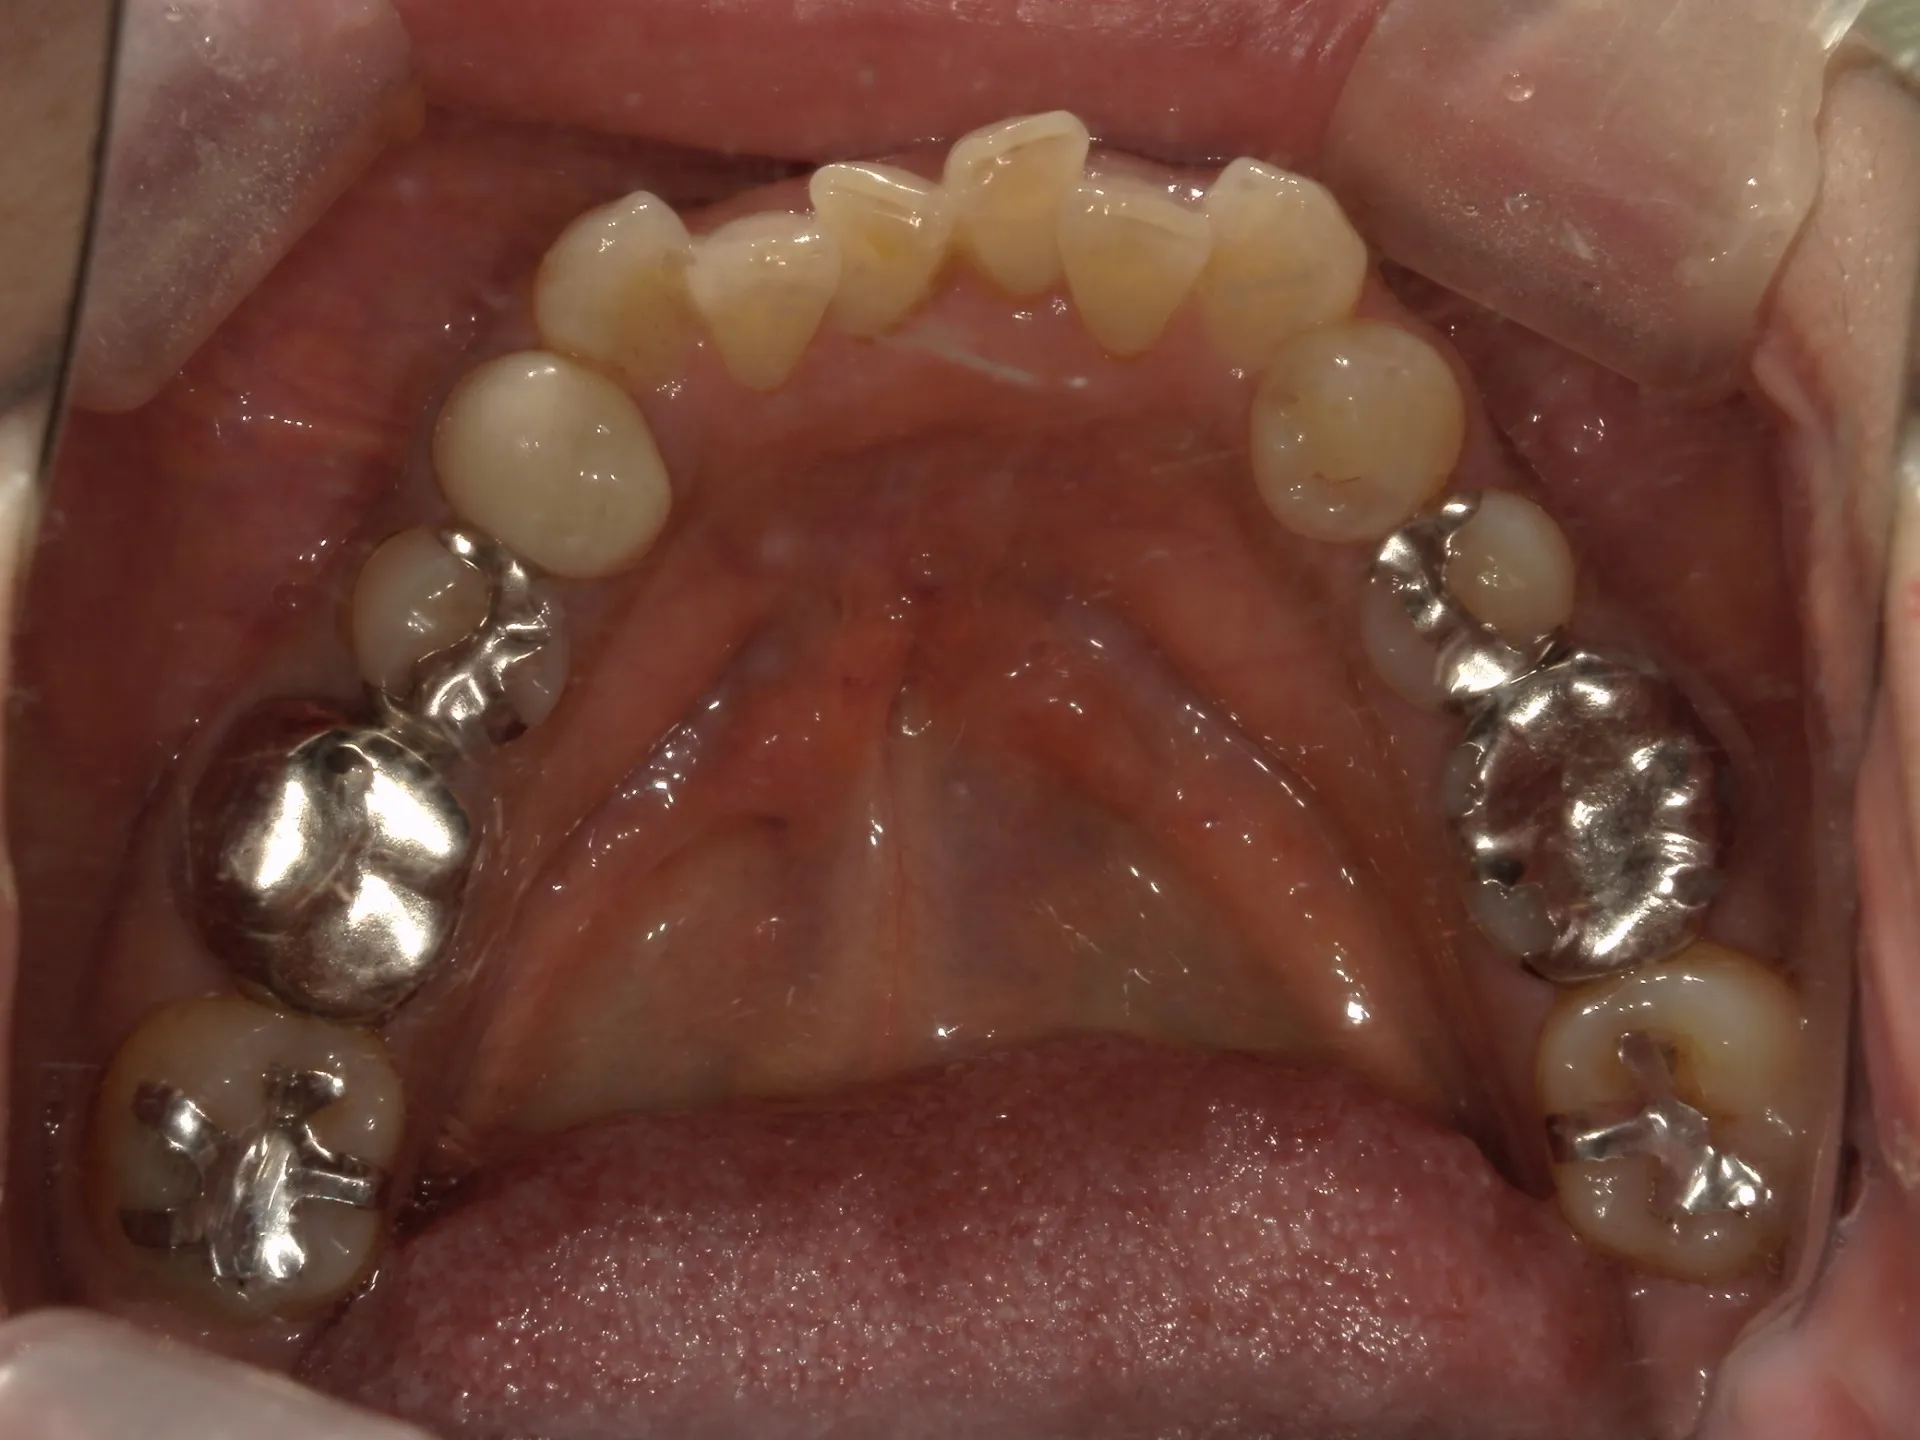

今回は65歳以上でも矯正治療を開始した症例についてご紹介いたします。

しかし、年齢がたとえ定年を迎えたあとであっても十分に矯正が行えて、今後の歯磨きが容易になり、虫歯や歯周病のリスクが減らせて歯を残すことが出来たり、歯並びが良くなったことでモチベーションも上がるなどの矯正後のメリットも非常に高いため、健康的な生活を行う上でも矯正治療は行うことをお勧めします。